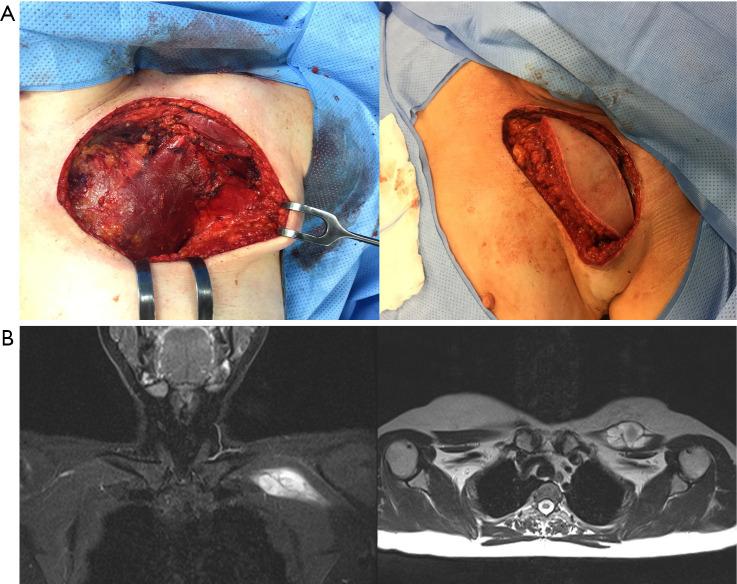

Chest wall sarcomas are rare and pose significant technical challenges in surgical management, particularly in patients with advanced disease. In this study, we examined the extent of resection, reconstruction techniques, and oncological outcomes of patients with chest wall soft tissue and bone sarcomas.

This retrospective single-center series included patients who underwent surgery at our center between May 2014 and February 2022 for deep-seated/subfascial primary and recurrent soft tissue or bone sarcomas of the chest wall requiring significant resection and extensive reconstruction. We analyzed clinical and operative data, including extent of resection, reconstruction techniques, and oncological outcomes. Additionally, we compared survival outcomes between patients with primary and recurrent tumors, and examined how these were influenced by clinical factors using Cox proportional hazards regression analysis.

Of the 38 patients included, 22 were treated for primary or recurrent soft tissue sarcoma (STS) and 16 for bone sarcoma. microscopic radical resection (R0) was achieved in 95.45% and 93.75% of patients with soft tissue and bone sarcomas, respectively. Nonetheless, local recurrence or distant metastases occurred in 40%, 58.33%, and 40% of patients with primary soft tissue, recurrent soft tissue, and bone sarcomas, respectively. Adherence to clinical guidelines and treatment in the reference center was high for bone sarcoma (93.75%), but notably low for STS, resulting in 54.55% of these patients requiring re-resection. Compared with those who underwent only one surgery, patients who underwent re-resection had poorer postoperative outcomes, more severe complications, and longer hospital stay.